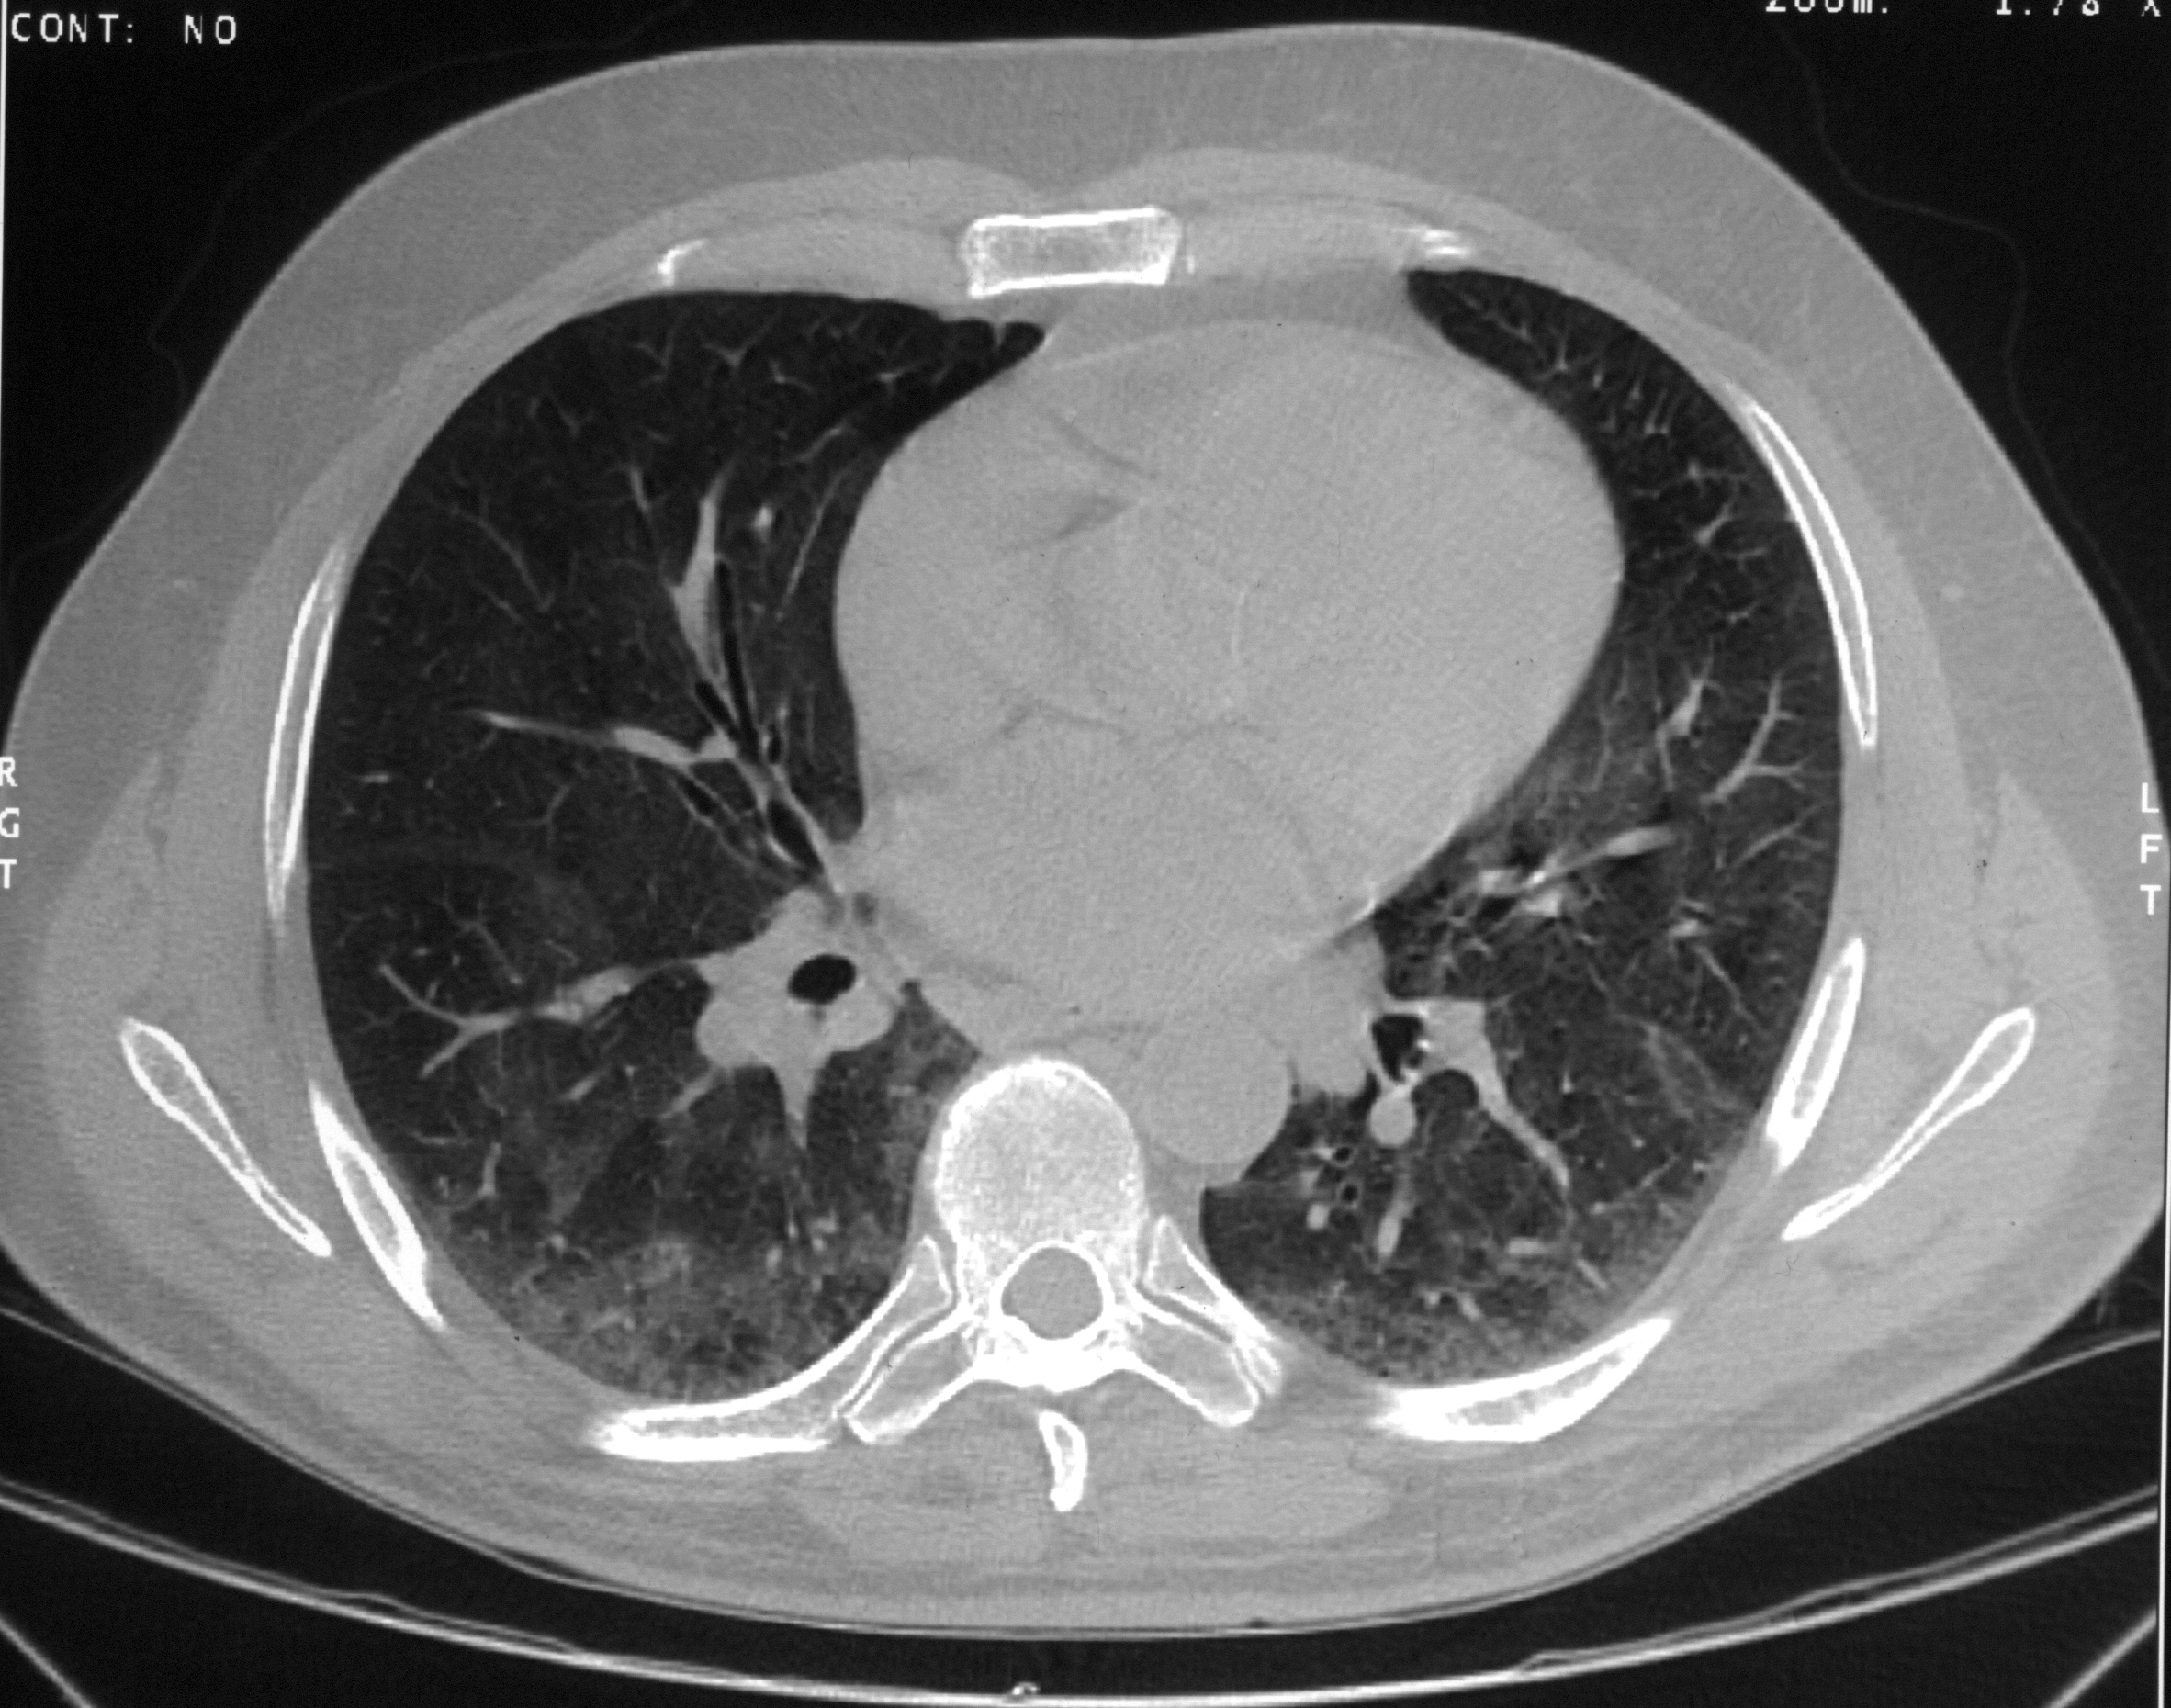

A thin-section computed tomography (CT) scan of the chest (Figure 2) showed "ground glass" opacities indicating interstitial lung disease, and mild bronchiectasis.

Figure 2: Thin layer CT scan of the chest showing patchy areas of increased interstitial markings.